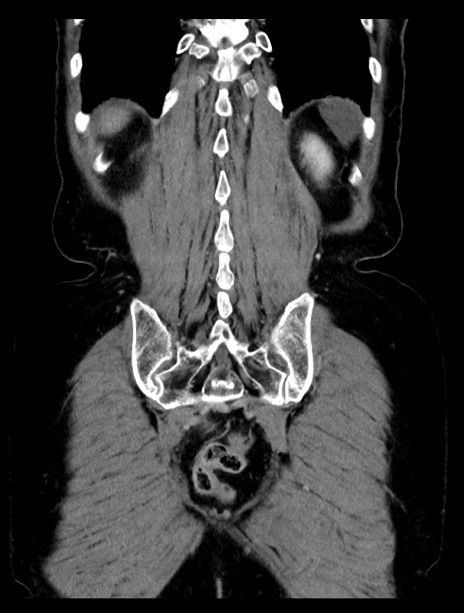

症例23(冠状断像)

【症例】70歳代女性

【主訴】下腹部痛・嘔吐

【現病歴】2日前より腹痛あり。昨日嘔吐あり。症状改善しないため来院。

【既往歴】胃GISTに対して胃部分切除後。

【身体所見】BT 37.1℃、BP 128/77mmHg、腹部:平坦・軟、下腹部に圧痛あり。

【データ】WBC 10200、CRP 0.31